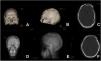

A 40-year-old Caucasian male suffered a traumatic brain injury that required a decompressive craniectomy. One month after initial trauma autologous cranioplasty was performed. A ventriculoperitoneal shunt was also placed. Neurological status progressively improved but his therapist noted cognitive status decline 8 months later. Follow-up computed tomography showed a progressive sinking bone flap. The patient underwent bone flap removal and a custom-made calcium phosphate-based implant was inserted, leading to symptoms resolution.

Bone resorption has been described as the main cause of sinking bone flap following cranioplasty. This entity may manifest with symptoms of overdrainage in patients with cerebrospinal fluid shunt devices.